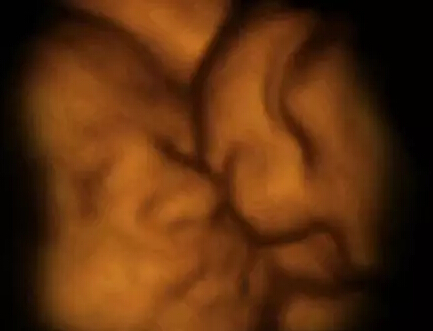

这张图见证了罕见的“双胎消失征”。图中居右的第3个胎盘是空的,这证明了多胞胎可能由于缺少营养而从子宫中消失。

这对双胞胎在进行头顶头的肉搏战。

有时候,这些推挤看起来像是升为了相互击打。